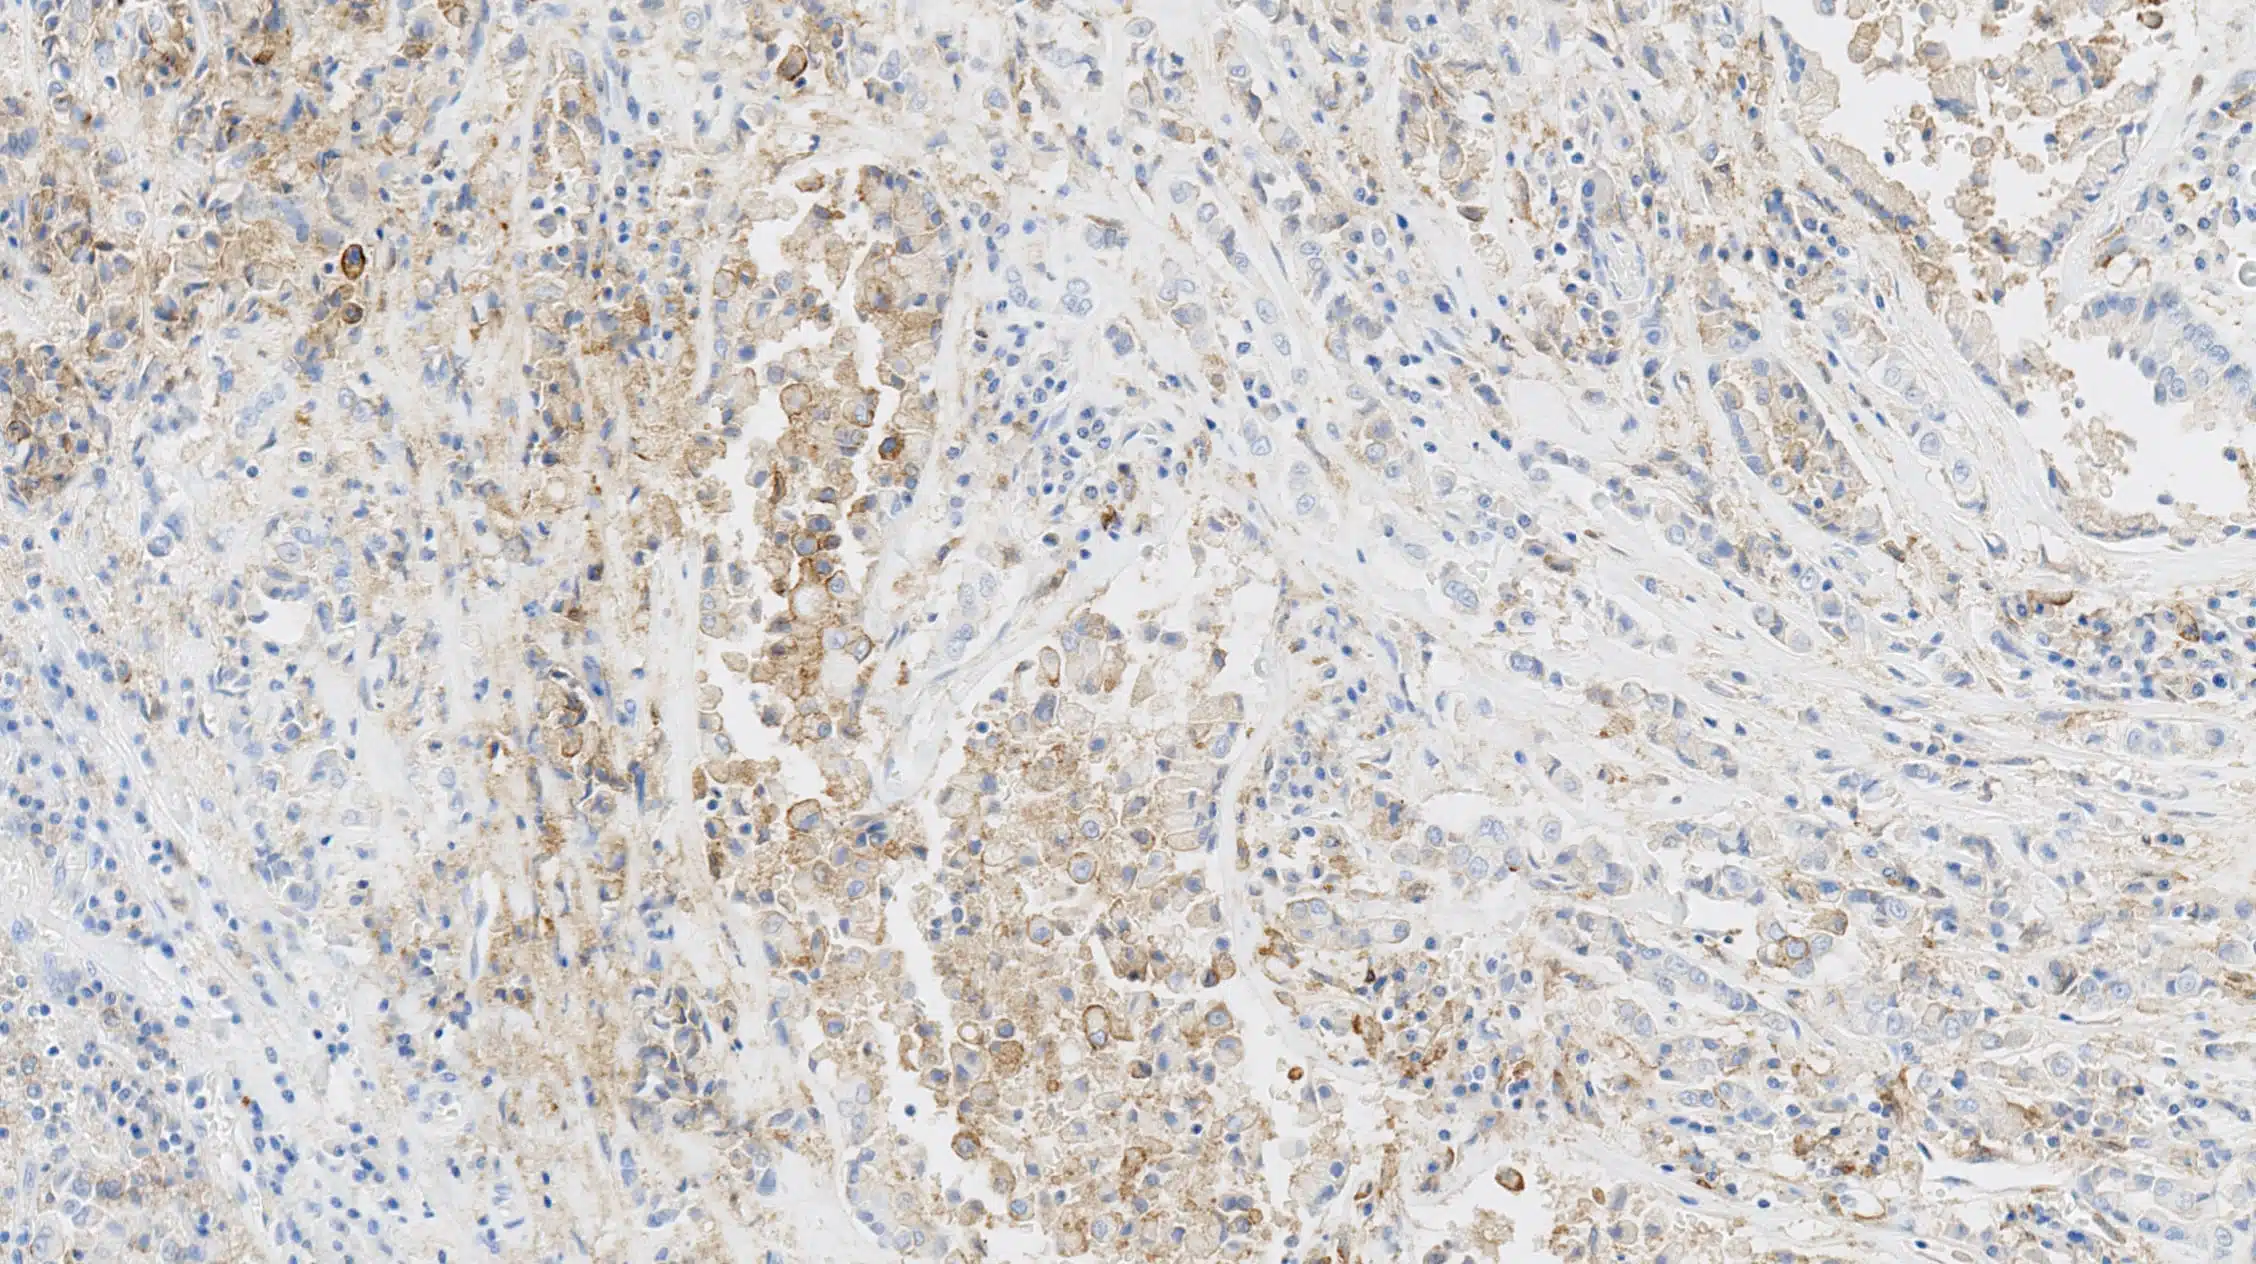

免疫組織化学(IHC)biomarkers技術により、腫瘍生検においてバイオマーカーを同定できる。IHCは、腫瘍の環境におけるバイオマーカーメカニズムをより深く理解する可能性を提供する。